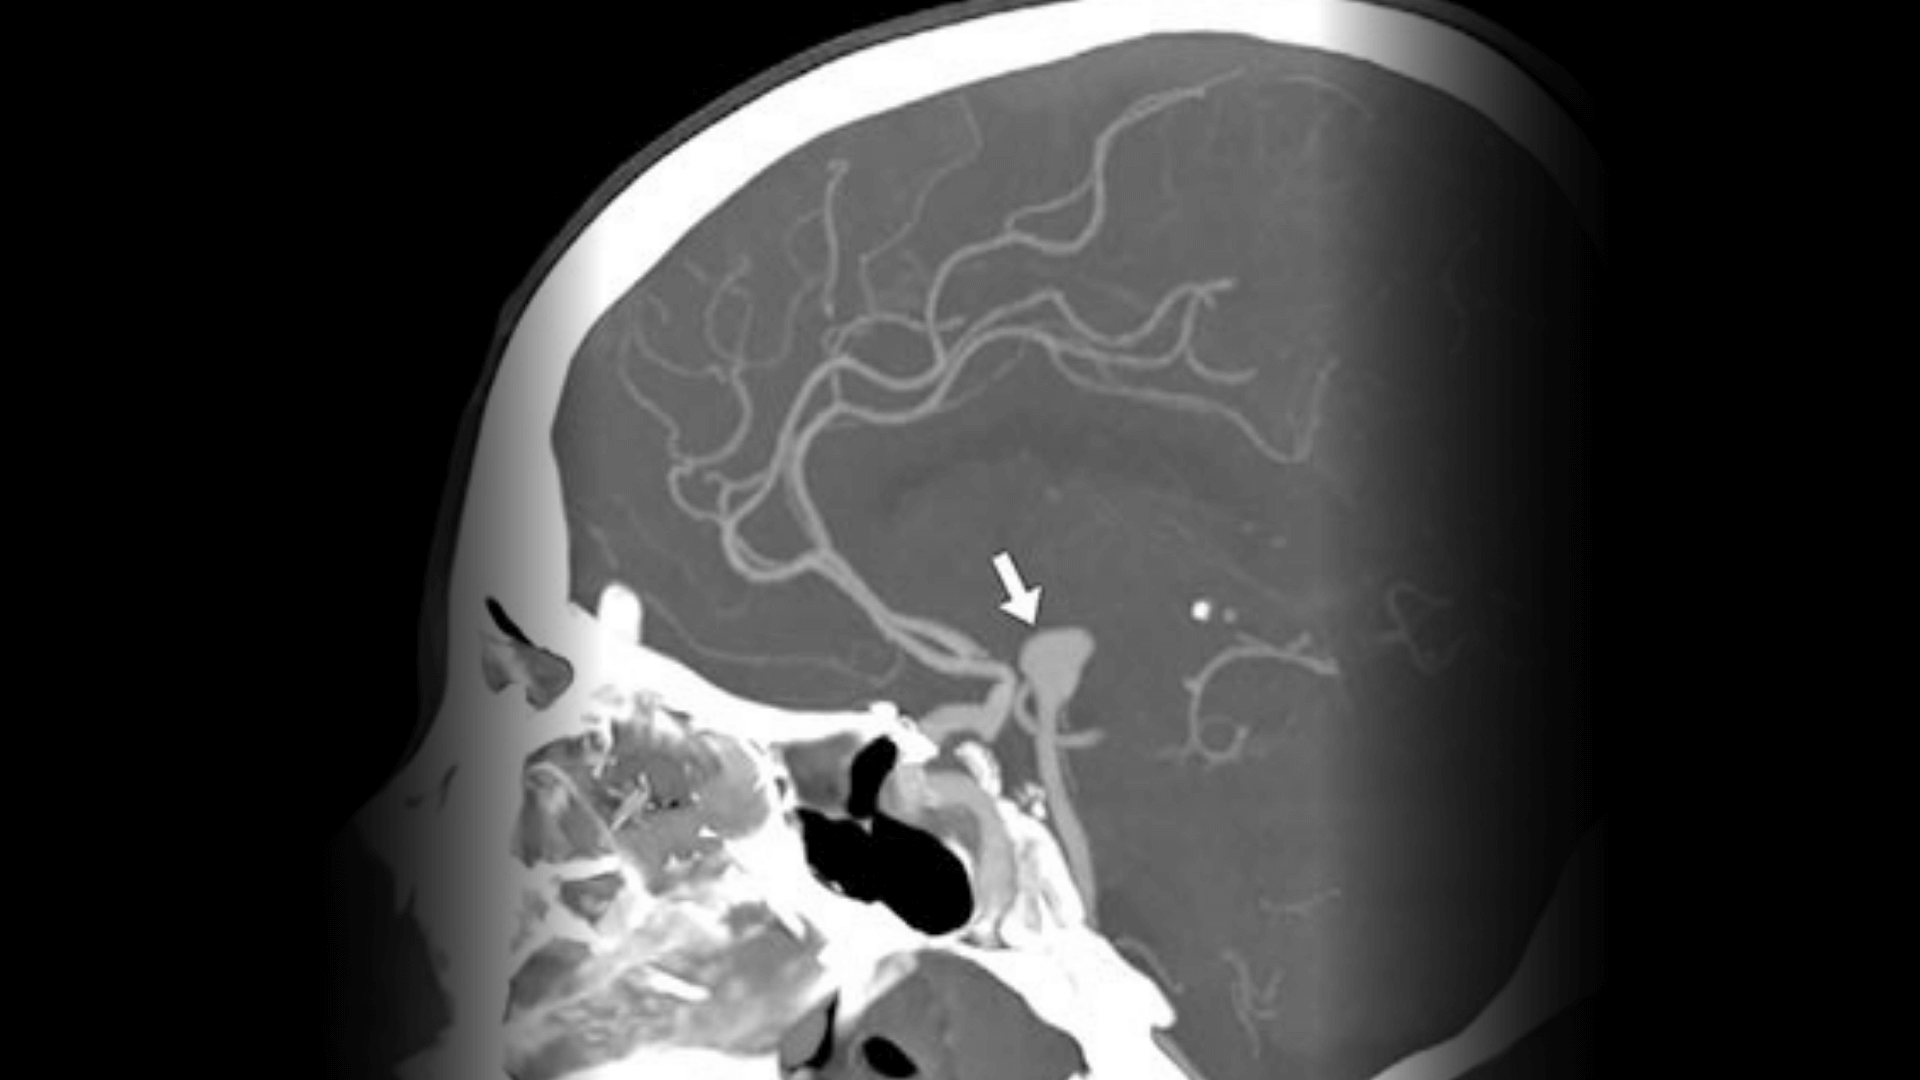

ANEURISMA CEREBRAL

O aneurisma cerebral é uma dilatação na parede de uma artéria do cérebro. Pode ser tratado por embolização, técnica minimamente invasiva que evita a ruptura do aneurisma.

O que é angiografia cerebral?

É um exame que avalia os vasos sanguíneos do cérebro para diagnosticar aneurismas, MAVs e estenoses carotídeas.

O que é um aneurisma cerebral?

É uma dilatação em uma artéria do cérebro que pode romper e causar um AVC hemorrágico.